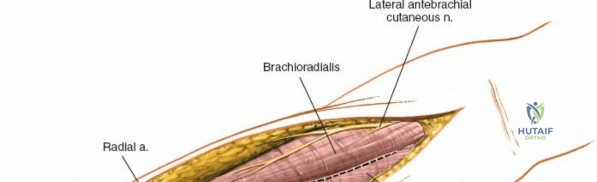

The anterior approach to the radius is an elegant example of utilizing true internervous planes to achieve deep exposure without denervating musculature. Distally, the internervous plane lies between the brachioradialis muscle (innervated by the radial nerve) and the flexor carpi radialis muscle (innervated by the median nerve). Proximally, the plane transitions to lie between the brachioradialis (radial nerve) and the pronator teres muscle (median nerve). Exploiting this plane allows the surgeon to mobilize the entire lateral muscular compartment (the "mobile wad" comprising the brachioradialis, extensor carpi radialis longus, and extensor carpi radialis brevis) away from the anterior flexor compartment.

Superficial Surgical Dissection and Internervous Plane

Incise the deep fascia of the forearm in line with the skin incision. The initial goal is to identify the medial border of the brachioradialis as it courses down the forearm. It is a common pitfall to search for this border too far laterally. At the level of the elbow, the brachioradialis is expansive and extends almost halfway across the anterior forearm. It is surprisingly easy to mistake the plane between the brachioradialis and the extensor carpi radialis longus for the correct intermuscular plane.

To confirm the correct plane, look for the superficial branch of the radial nerve. This sensory nerve runs on the undersurface of the brachioradialis muscle. Once the true medial edge of the brachioradialis is found, develop the plane between it and the pronator teres (proximally) or the flexor carpi radialis (distally). Retract the brachioradialis laterally, taking care to keep the superficial radial nerve attached to its undersurface to protect it from traction injury.

Managing the Radial Artery and Recurrent Leash

As the brachioradialis is retracted laterally, the radial artery and its venae comitantes are exposed lying deep in the middle part of the forearm, closely related to the medial edge of the wound. Begin dissection distally and work proximally. Just below the elbow joint, the radial artery gives off the recurrent radial artery and a leash of muscular branches that dive laterally into the brachioradialis.